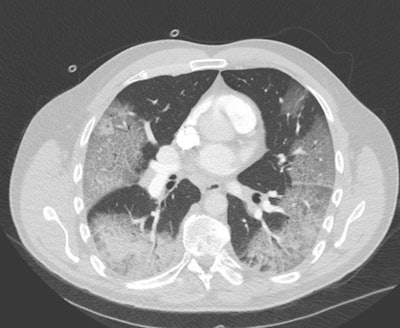

"COVID-19 causes a wide variety of findings on these scans, most typically ground-glass type of densities located on the outside of both lungs (see white areas in figure)," he continued. "The accuracy of chest CT to diagnose COVID-19 has been reported as high and can predate a positive classic serological RT-PCR test. Therefore, in endemic areas where the healthcare system is under pressure, hospitals with a high volume of admissions are using CT for rapid triage of patients."

CT scan of a COVID-19 patient who was originally referred for CT angiography of the chest to exclude pulmonary embolism. The ground-glass opacifications are clearly depicted, with a consolidation in the right lower lobe.There is a role for chest CT to assess COVID-19 infection in patients with severe and worsening respiratory disorders. Based on the images, doctors can evaluate how severely the lungs are affected and how the patient's disease is evolving, which is helpful in making treatment decisions, according to Ranschaert.